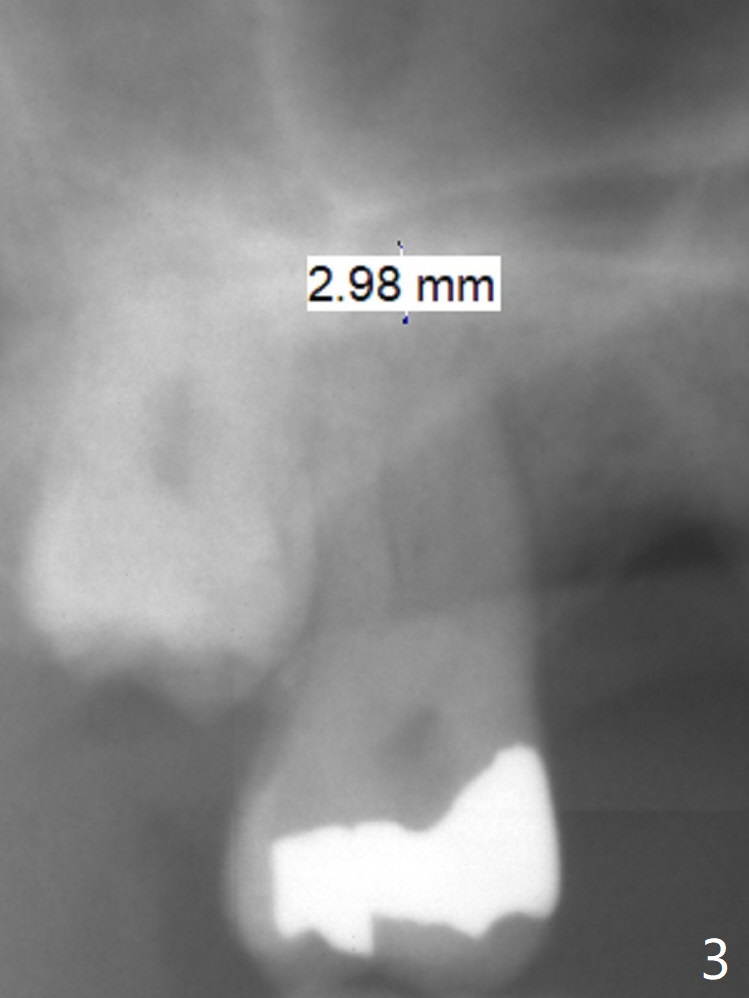

A 58-year-old man had 2 missing molar 3 years ago (Fig.1). Later the tooth #2 fractures with apparently severe bone loss (Fig.2). If the septum is lost, bone height is around 3 mm (Fig.3). Take PA before using Magic Sinus Lifter. Since his bone density is high, increase exposure time. If the septum is present (Fig.4), use Magic Drills sequentially (1.6, 2.8, 3.2 mm ....). PRF plug and membrane (1 each) are to be prepared.